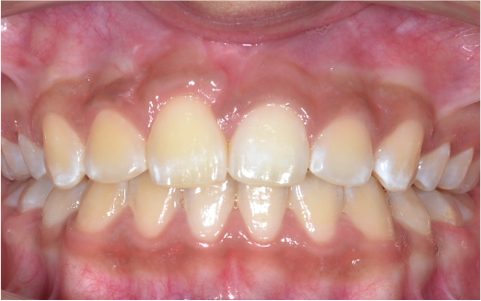

Traccion de un diente retenido

Después